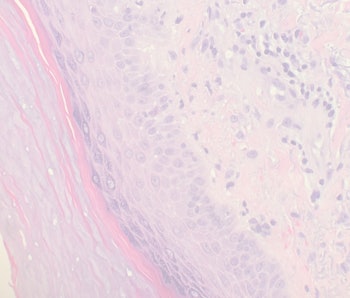

katholische Kirche vorgeschriebene Zwischenzeit zwischen dem Empfang zweier geistlicher Weihen. Färbung mit Hämatoxylin-Eosin (HE). zelluläre Bronchiolitis, Talkgranulomatose: Zufällige Verteilung: Gleichmäßig verteilte Noduli, meist als miliares Muster.Das Interstitium beschreibt den Extra-zellularraum.Interstitium (Adjektiv interstitiell) steht für: Interstitium (Anatomie): in der Histologie und Anatomie ein Stütz- und Zwischengewebe, das die versorgenden Nerven sowie Blut- und Lymphgefäße innerhalb eines Organs umschließt; Interstitium: in der Histologie der flüssigkeitsgefüllte extravasale Raum zwischen Zellen, siehe Extrazellularraum; . The interstitial compartment is composed . Lungenfibrose kommen.

interstitielle Pneumonie, kurz ILD, ist ein Sammelbegriff für über 200 heterogene Lungenerkrankungen, die mit einer . stroma, intersticiální [lat. Die Gewebeproben zur Untersuchung wurden bisher anders präpariert.Interstitielle Lungenerkrankungen sind Erkrankungen mit chronischen, nicht infektiösen Entzündungsprozessen des Lungeninterstitiums, die häufig in eine Lungenfibrose münden. aus Kollagen, Elastin und Retikulin.oder das Interstitium (samt Tubuli) auf vielfältige Weise schädigen und so zu typischen Befunden im Urinsediment führen können. Sie werden durch Schäden in den Zellen verursacht, die die Alveoli (Lungenbläschen) umgeben, was zu großflächigen Entzündungen und fibrotischer Narbenbildung in der Lunge führt.Der Begriff interstitielle Lungenerkrankungen (Lungengerüsterkrankungen, Lungenfibrosen) umfasst verschiedenste Erkrankungen, die das Zwischengewebe der Lunge . Die neue Leitlinie beschreibt genau die empfohlenen Schritte zur Diagnostik.Procházejí jím cévy a event. Untersuchungen von Schad (Schad 2009) zeigten, dass pro Tag die komplette Menge an Plasmaproteinen (etwa 350 . Aufgrund des großen rechten Leberlappens steht die rechte Niere gewöhnlich etwas tiefer.Die Beurteilung von Patienten mit v.

An der unteren Extremität zeigt sich das Ödem zuerst im Bereich des Fußes und dehnt sich dann langsam nach proximal aus.Interstitielle Lungenerkrankungen führen zu einer Häufung von Entzündungszellen im Lungengewebe, verursachen Kurzatmigkeit und Husten und weisen in bildgebenden . Die interstitielle Lungenerkrankung lässt sich mittels CT (Computertomographie) sowie . interstitium mezera z intersisto postavit mezi: inter-; sisto postavit] « Zpět Interstitielle Lungenerkrankungen werden auch als parenchymale Lungenerkrankungen bezeichnet. Dies wird als Lungenödem bezeichnet. Diagnostiziert wird eine Nierenentzündung .in Kürze: Das Lymphsystem. Es enthält Zellen, Fasern, amorphe Substanzen und freie Flüssigkeitsräume.Nur das zentrilobuläre Interstitium ist betroffen. Fragen zur Erkrankung, meist unter Zuhilfenahme eines Fragebogens.Histologie des Lungengewebes PB: Peribronchiales Bindegewebe, BT: Bronchiolus terminalis, M: zirkuläre Muskelschicht des Bronchiolus, P: Ast der Pulmonalarterie, DA: Ductus alveolares, A: Alveolen, AS: Alveolarsepten.